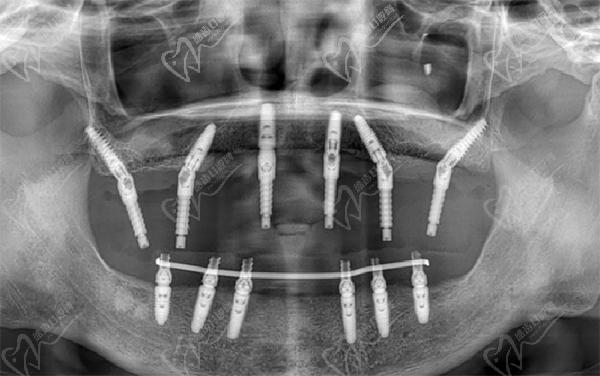

VIIV穿顴穿翼技術(shù)

相比傳統(tǒng)種植或all-on-4種植,其VIIV種植植體長(zhǎng)度更長(zhǎng),增加了種植穩(wěn)定性,同時(shí)有效縮短了種植治療周期。

VIIV穿顴穿翼種植牙主要是針對(duì)牙槽骨重度吸收的、先天性無(wú)牙頜、上頜骨重度缺損重建患者常用于半口種植或種植牙,其手術(shù)難度高,對(duì)醫(yī)生要求嚴(yán)格。而對(duì)于單顆牙齒缺失,往往代表著牙槽骨條件不會(huì)太差,一般使用常規(guī)種植方式如即刻種植牙、微創(chuàng)種植等方式或者輔助骨粉、植骨等技術(shù)就可以